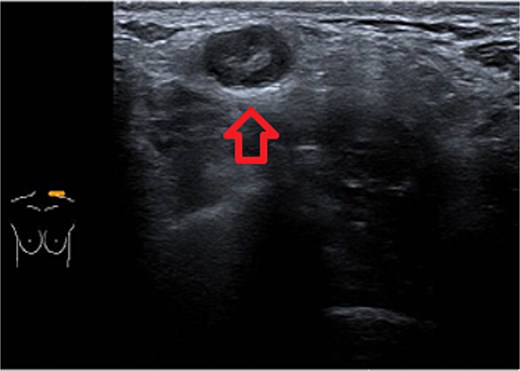

Ultrasound of left breast and axilla: Revealed rupture of the left implant with intracapsular and extracapsular leakage, along with echogenic peri-implant fluid. Enlarged axillary lymph nodes were visualized (Figs 1 and 2).

Ultrasound of the left breast showed rupture of the left breast implant with intracapsular and extracapsular leakage, surrounded by echogenic peri-implant fluid.